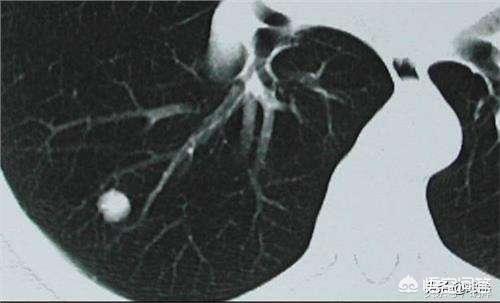

肺部结节根据密度不同分为不同类型,密度较高,在胸部CT上变现为白色小点的称为实性结节,磨玻璃结节则密度较淡,像是哈在玻璃上的水汽,两种结节的处理并不是特别一样,相对来说磨玻璃结节或者内部实性又伴有磨玻璃的混合型结节处理起来不太一样,磨玻璃结节,尤其是纯磨玻璃结节更倾向于恶性。

一般来说6mm以下不用太担心

一般6mm以下的结节偏良性的多一些,有人会说,恶性肿瘤不也是从1mm一点一点的长起来的吗?这里有一个概率问题,一般来说良性病灶小且比较稳定,大部分停止在6mm以下,因此被很小的时候查到的机会比较大,而恶性肿瘤特别是恶性程度比较高的肺癌,生长较快,所以容易被在较大的阶段发现,6mm以下结节可以在初发现时密切随访复查胸部CT,以后逐渐拉长复查的间隔时间,如果一直不变化,最终可以拉长到一年检查一次。

直径在1cm以上的结节要进一步检查

直径在1cm以上的结节恶性可能性比8mm以下的结节要大很多,需要到医院检查一下,那为什么不在8mm的时候就做检查呢,一方面由于结节太小,其内部的性质以及细胞活跃程度并没有和周围的细胞明显的区分开来,无创检查比如PETCT还无法将之辨别出来,另一方面由于结节太小,做气管镜和肺穿刺等肿瘤确诊性有创检查又无法准确的取到标本,所以大部分情况下只有当结节超过1cm的时候才采取行动,但并不代表小于1cm的结节就可以不重视,一般来说超过6mm又小于1cm的结节要么密切随访,要么在发生增大的时候手术切除,没有其他的方法可以有效的分辨结节的性质。